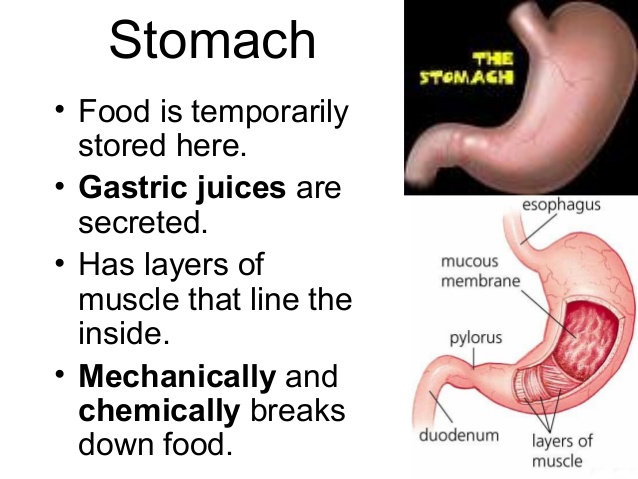

The stomach is a sac-like organ that provides temporary storage for swallowed food. Carbohydrate is churned into chyme (semi fluid food), mixed with gastric juice, acidified and the bacteria in the food are killed. Proteins are also churned into chyme, and the enzyme called pepsin digests proteins into peptones. Enzyme called rennin changes fat in milk into semi solids.

The stomach is a sac-like organ that provides temporary storage for swallowed food. Carbohydrate is churned into chyme (semi fluid food), mixed with gastric juice, acidified and the bacteria in the food are killed. Proteins are also churned into chyme, and the enzyme called pepsin digests proteins into peptones. Enzyme called rennin changes fat in milk into semi solids.